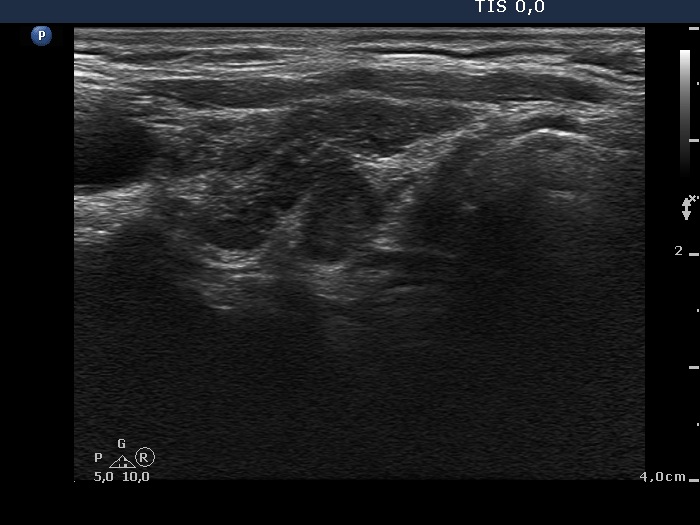

Intranodular hyperechogenic figures - case 41

Follow-up examination 2 years later (ultrasonographic picture 2)

Right lobe, longitudinal scan. There are several discrete lesions divided by fibrous septa.